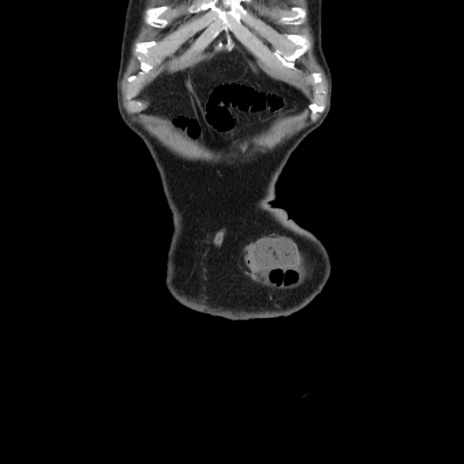

横断像